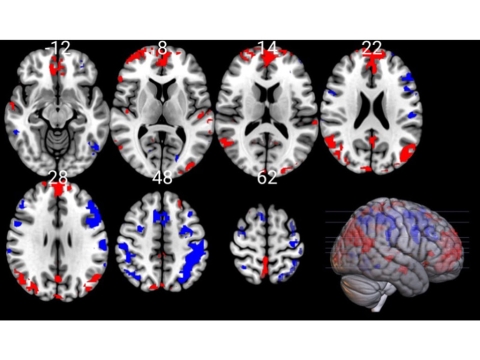

Layers of the MRI scan also showing increased activity in the medial prefrontal cortex and parietal cortex

MRI scan of the brain showing the parietal cortex (left) and medial prefrontal cortex (right) as red after a cold water bath - indicating increased activity compared to the areas showing in blue

Comparing the scans showed that changes had occurred in the connectivity between specific parts of the brain, in particular, the medial prefrontal cortex and the parietal cortex.

“These are the parts of the brain that control our emotions, and help us stay attentive and make decisions,” Dr Yankouskaya said. “So when the participants told us that they felt more alert, excited and generally better after their cold bath, we expected to see changes to the connectivity between those parts. And that is exactly what we found.”